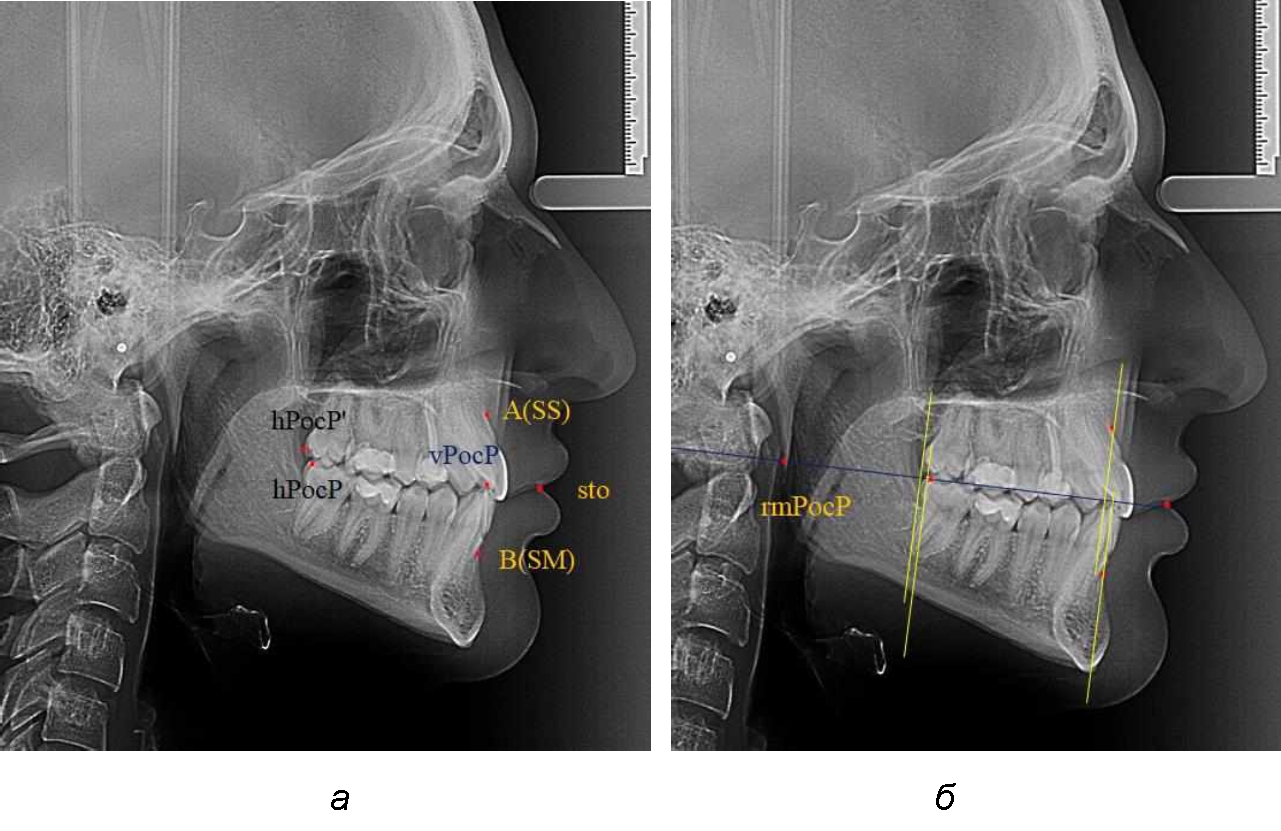

При всех вариантах положения верхней челюсти, было отмечено, что альвеолярно-денталь-ные размеры верхних зубо-челюстных дуг были близки по значению к аналогичным размерам нижней челюсти и разница в размерах не превышала 1,0–1,5 мм, а средняя величина различия показателей составляла (1,07 ± 0,54) мм.

Расстояние от конструируемой точки окклюзионной плоскости на ветви челюсти («rmРOcP») до апикальных точек Downs на обеих челюстях также коррелировало между собой, и средняя величина различия показателей составляла (1,23 ± 0,69) мм. Проекция нижней апикальной точки на окклюзионную линию, как правило, располагалась несколько кпереди проекции верхней апикальной точки, на величину около 1 мм, что соответствовало оптимальным данным Wits-анализа.

Аналогичное расстояние было отмечено и при расположении дистальных окклюзионных точек верхней и нижней челюсти (рис. 2).

Рис. 2. Положение апикальных точек и челюстей при нормопозиции (а), антепозиции (б) и ретропозиции (в) верхней челюсти